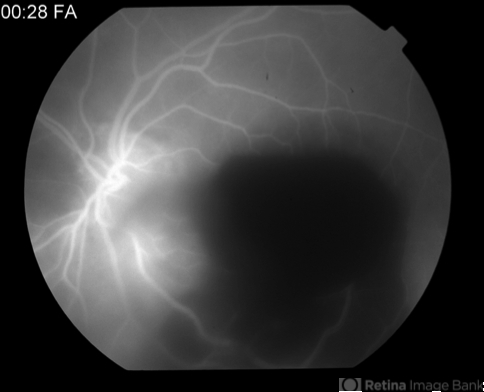

Early Phase Angiogram Showing Vitreous, Preretinal and Subretinal Hemorrhage

A 90-year-old woman presented with sudden loss of central vision OS of 1 week. Her VA was finger counting OS, with mild-moderate vitreous hemorrhage and large preretinal and subretinal hemorrhage, felt to be due to AMD or retinal artery macroaneurysm.